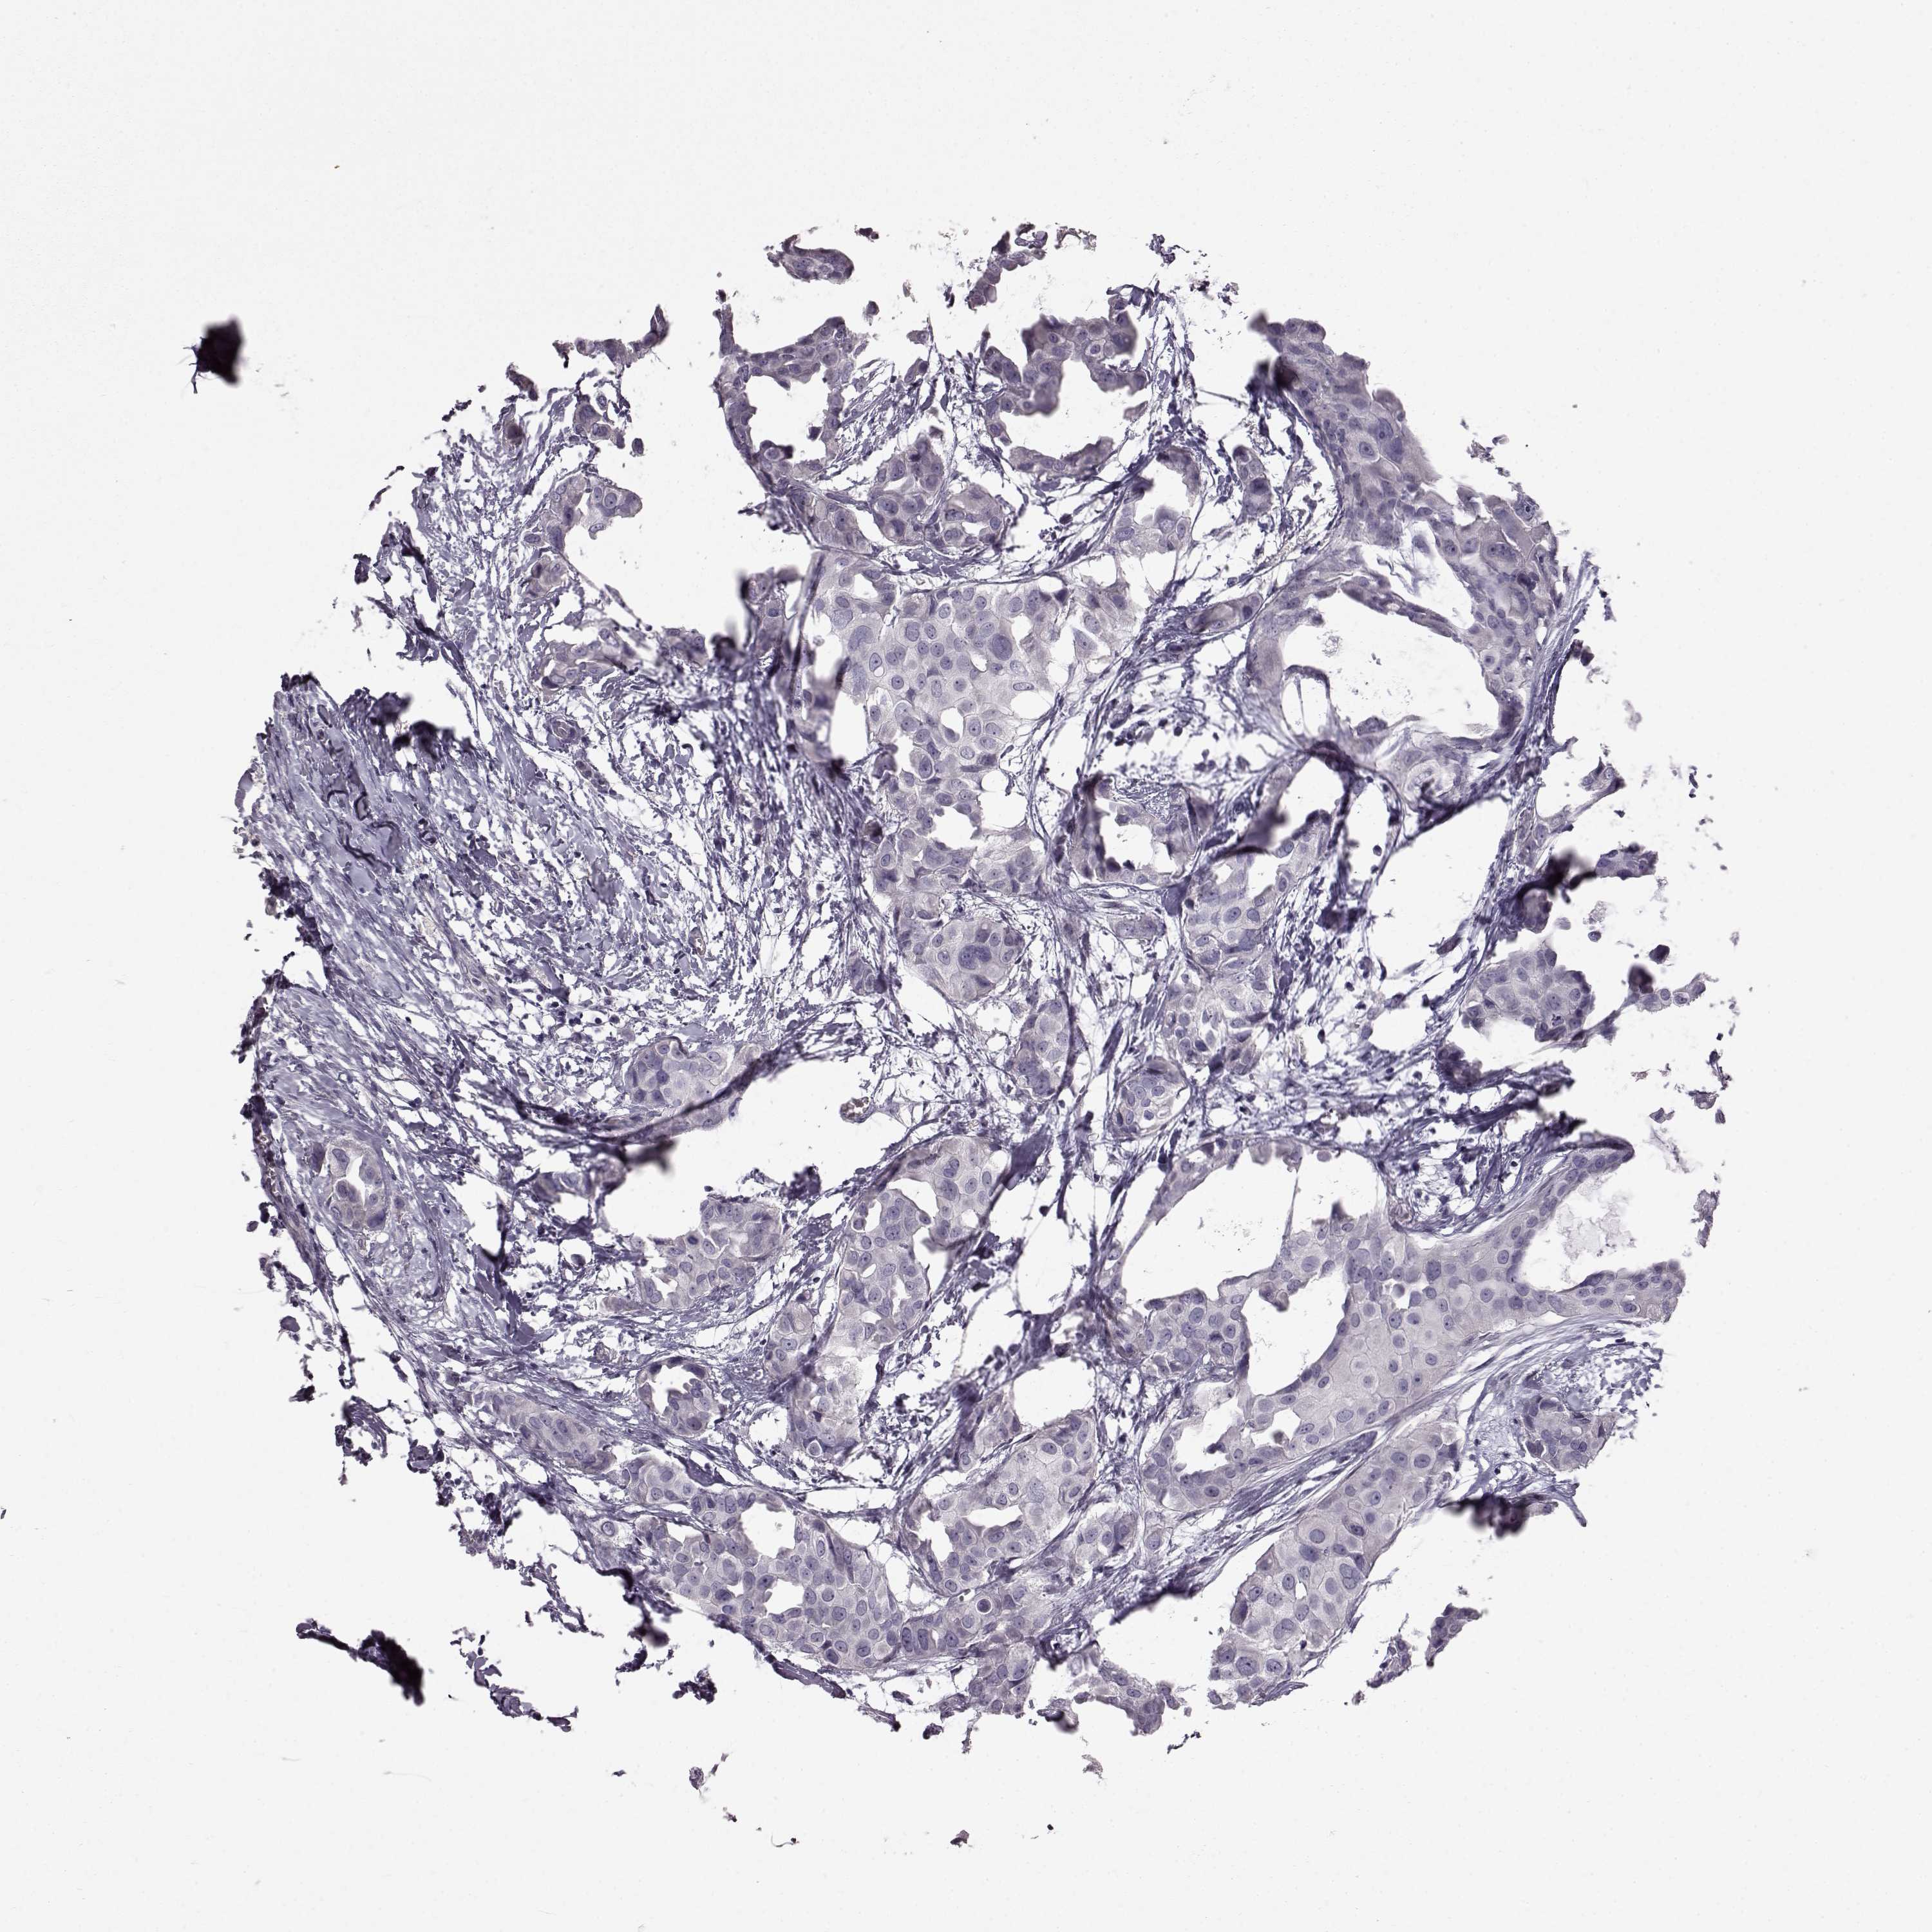

Breast cancer

Human cancer